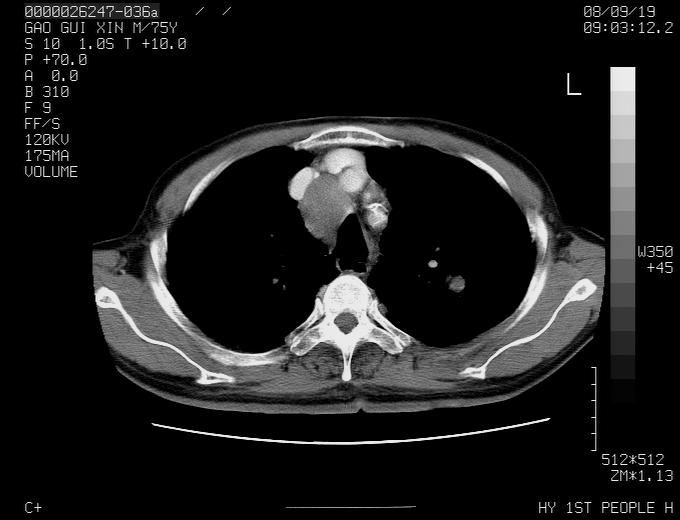

感谢各位老师的意见,左上肺病灶,我本人趋向结核,原因:左上肺见两个类圆形结节,仔细回顾4月份ct似乎原片在该处有条片状密度增高影,强化不明显。

现上传增强片,请各位老师仔细帮我看一下。

右上肺可见条索状影,并可见钙化,左上肺结节可以考虑为结核球,但气管前腔静脉后有肿大淋巴结,本人觉得左上肺结节不能排除转移瘤的可能,右上肺为陈旧性结核灶。

左肺上叶周围性肺癌并纵隔多组lnm.不可能是tb.

左肺上叶尖段瘢痕癌并纵隔淋巴结转移解释更好一些.

1)左肺上叶尖段周围型肺癌并纵隔淋巴结转移。2)冠状动脉及主动脉钙化。